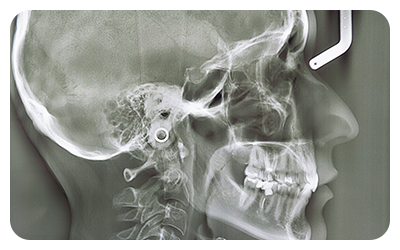

当院には、高精度な型取りができる口腔内スキャナーや、骨の状態などを詳しく確認できる歯科用CT、頭部専用のセファロレントゲンなどの設備が充実しています。こうした先端設備を活かして、なるべくお子様の負担が少なくなるような診断・治療を行っています。一人ひとりのお子様のお口の状態をしっかりと把握し、適切な治療の提供に努めています。

矯正治療を検討される場合は、治療計画の作製に必要なデータを収集するための精密検査を行います。歯科用CTや頭部専用のセファロレントゲン、口腔内スキャナーなどを使って精密なデータを収集し、経験豊富な歯科医師がお子様に合わせた治療計画を作製します。